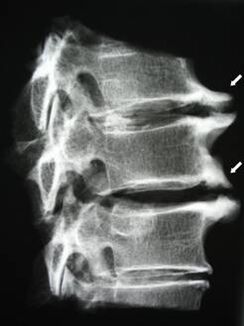

V začetnih fazah se osteohondroza odkrije z MRI. Kasneje lahko patologijo diagnosticiramo z radiografijo. Na radiografiji vratne hrbtenice je opazno zmanjšanje razdalje med vretenci, patološke spremembe v fasetnih sklepih in osteofitoza.

| Cervikalna osteohondroza | Pojav patoloških sprememb v enem ali več segmentih gibanja hrbtenice. Motena gibljivost hrbtenice, razvoj miofascialnih bolečinskih sindromov in stiskanje hrbteničnih korenin. | Bolečina, parestezija in motorične motnje v predelu materničnega vratu, ki se razširijo na zadnji del glave in zgornje okončine. Odkrivanje značilnih sprememb hrbtenice na MRI in rentgenskih slikah (osteofiti, zmanjšana razdalja med vretenci, znaki poškodb medvretenčnih sklepov) |